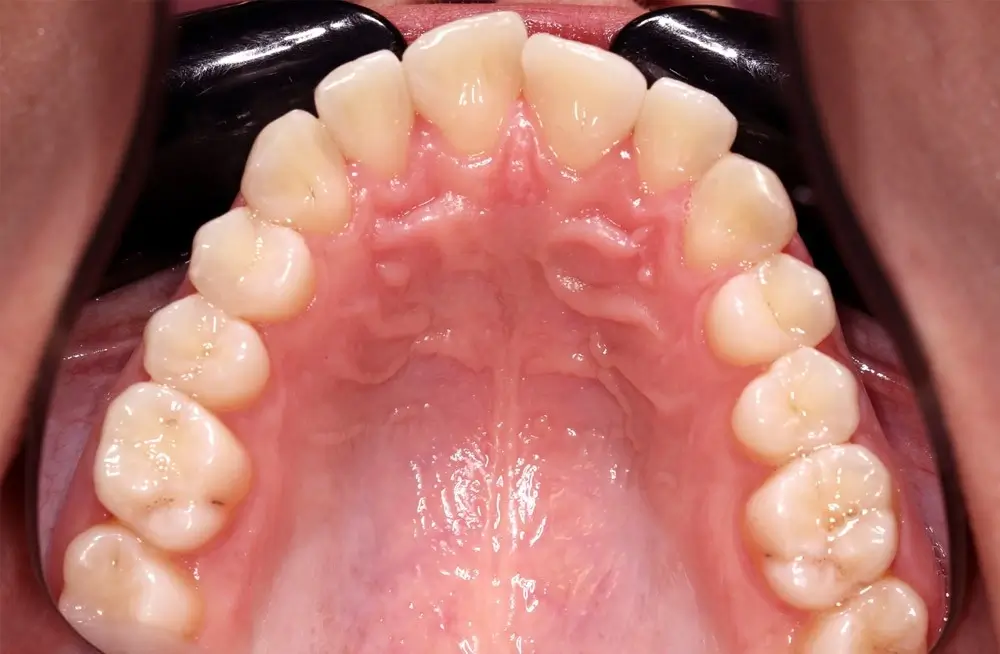

Скученность - Кейс 10

Эффективность устранения дефекта прикуса посредством элайнеров FlexiLigner.

16

Количество кап НЧ

Количество кап ВЧ

Результаты лечения